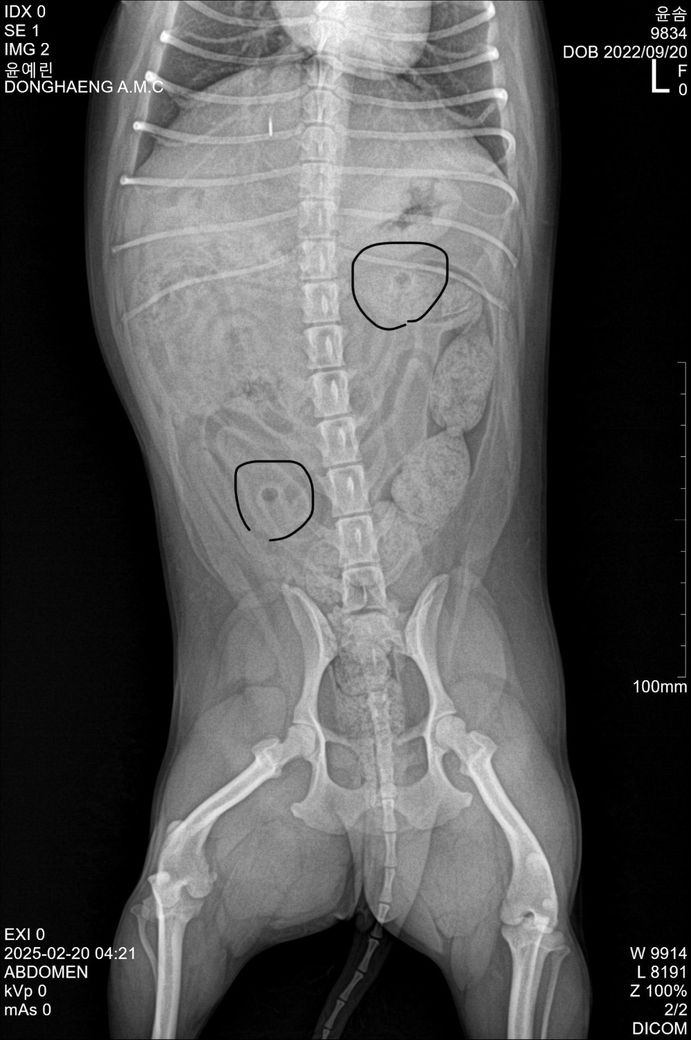

몇일전에 2년 8개월된 말티푸 강아지가 이물질먹고 구토를 계속 해서 동물병원에서 엑스레이를 찍었는데 이거 결석인지 의심되서요 고관절도 사진상 쪼금 안좋아보이긴한데 아닐꺼라고 하셨는데 다른분들의 의견도 궁금합니다

걸을때 엉덩이가 씰룩되긴해요

결석이 맞을까요?ᩚ 아님 뭘까요?ᩚ?ᩚ ㅠㅠ

작성자분께서 동그라미 친 곳은 결석이 아닙니다. 소장의 분절들이 엑스레이에서 나오는 빔을 수직으로 받아서 생긴 것입니다

가스가 충진된 장 분절이 방사선 빔과 수직으로 닿으면서 영상화된 모습입니다. 즉, 결석이 아닙니다.